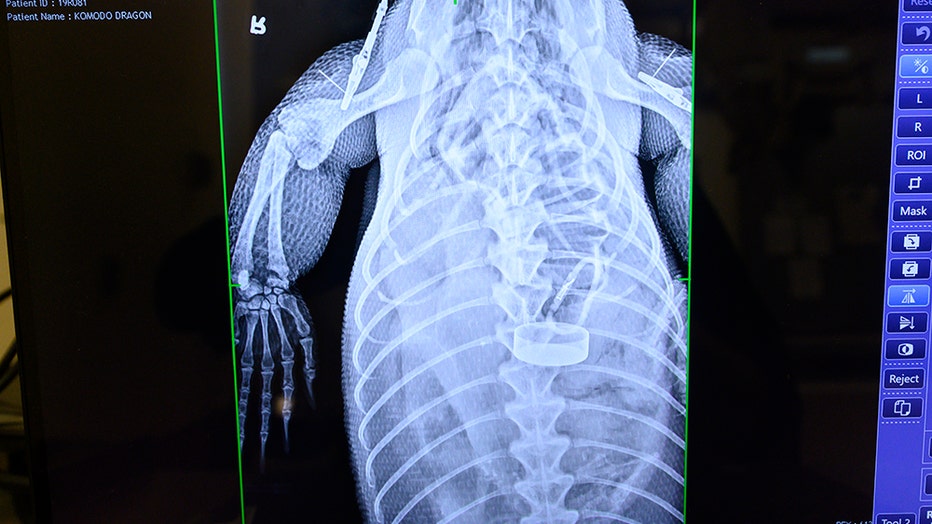

Komodo dragon undergoes emergency surgery after eating water bottle dropped into zoo enclosure

A Komodo dragon at Zoo Miami needed emergency surgery to remove a water bottle after officials say a visitor dropped it into the animal's enclosure.

The 9-year-old reptile, named Estrella, had to undergo the risky procedure because she would have died from a severe obstruction, zoo officials said.

“We had to pull out this massive, it was about a foot long, this water bottle with a metal cap on it and a clip at the end, the whole nine yards,” said Zoo Miami's Ron Magill.

The bottle was too large to be naturally passed and could not be extracted by endoscopy, according to zookeepers. The surgery to remove it took nearly three hours.